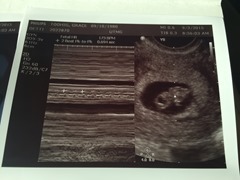

August 28th- Second ultrasound at 7 weeks 5 days. Heart rate 160. Spiffer came along and cried the whole time.

September 3rd- Third ultrasound at 8 weeks 3 days. Heart rate of 173. Jeanne came along and was in complete awe.

September 10th- Fourth ultrasound at 9 weeks 3 days. Heart rate of 166. We saw the baby DANCING. No kidding. Like waving his/her hand and bopping his/her head. WILD.

Sept 15th- Consultation with a great doctor at the Center for High Risk Pregnancies. He is a wonderful man, and we discussed the HELLP Syndrome that I had with HG’s pregnancy. The chances are very low that it will return this time, and I’m confident that he’ll monitor me closely. I got to see amazingly clear pics from their fancy ultrasound machine. Heartbeat was 172.

Sept 18th- Last ultrasound with Dr. Detti and both grandmamas came. 10 weeks 4 days. Lots of hugs and tears (from Spiffer) as we said thank you and goodbye to the team, as I’m transferred to my OBGYN.